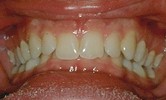

Avant Après

Avant

Après